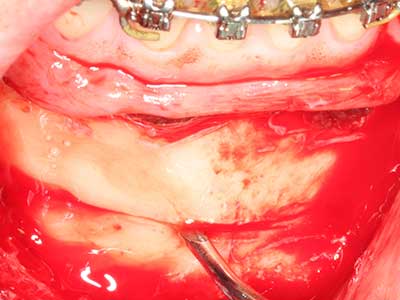

La preparación de la ventana lateral en la elevación del suelo del seno maxilar representa un enorme reto, sobre todo para profesionales de la implantalogía que tienen poca experiencia en técnicas quirúrgicas. Retirar la cobertura ósea del seno maxilar sin provocar daños en la membrana de Schneider es tan solo una parte de la operación; tras crear un acceso suficiente, es preciso movilizar con cuidado la mucosa del seno maxilar a fin de dejar espacio para el material o los implantes que vayan a incorporarse. En esta aplicación la cirugía piezoeléctrica resulta útil en dos sentidos: por un lado, el uso de insertos diamantados permite realizar una retirada selectiva del hueso y, si se actúa con cuidado, la membrana permanece intacta, y por otro lado, las frecuencias de ultrasonidos favorecen también un desprendimiento sin problemas de la membrana, pues se transfieren al espacio comprendido entre la mucosa y el suelo del seno maxilar gracias al uso de piezas romas especiales (Cassetta, Ricci et al. 2012, Pereira, Gealh et al. 2014) (Rickert, Vissink et al. 2013). De este modo, no es de extrañar los trabajos publicados en la actualidad sobre la técnica de elevación del suelo del seno maxilar mediante la técnica de Caldwell-Luc con instrumentos piezoeléctricos (Wallace, Tarnow et al. 2012).

Imágenes casos de aplicación clínicos